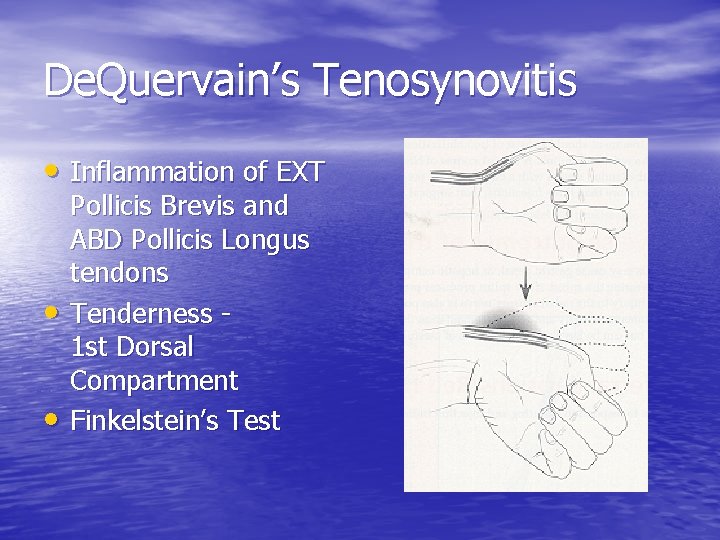

De. Quervain’s Tenosynovitis • Inflammation of EXT • • Pollicis Brevis and ABD Pollicis Longus tendons Tenderness 1 st Dorsal Compartment Finkelstein’s Test